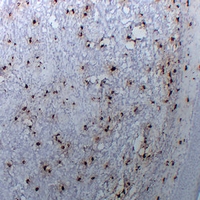

(Dilution: IH: (1/100 - 1/300)Immunohistochemical analysis of Tryptase alpha/beta staining in human liomyoma formalin fixed paraffin embedded tissue section. The section was pre-treated using heat mediated antigen retrieval with sodium citrate buffer (pH 6.0). The section was then incubated with the antibody at room temperature and detected using an HRP conjugated compact polymer system. DAB was used as the chromogen. The section was then counterstained with haematoxylin and mounted with DPX.)